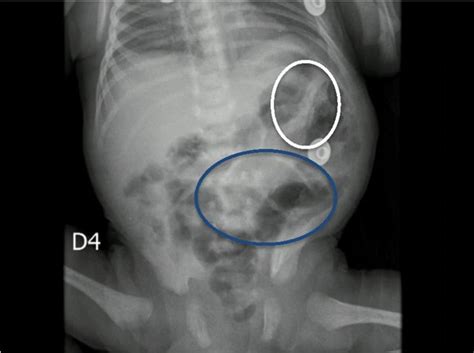

El diagnóstico de ECN se basa en el examen clínico y estudios de imagen. El proveedor de atención médica buscará signos de la enfermedad y puede solicitar una radiografía abdominal. Esta puede revelar un aspecto "burbujeante" de los intestinos, indicativo de aire o gas, e incluso detectar aire en las venas principales del hígado o fuera de los intestinos, lo que sugiere una perforación intestinal. En algunos casos, puede ser necesario realizar un drenaje de la cavidad abdominal para eliminar líquido infectado y permitir una mejor evaluación.